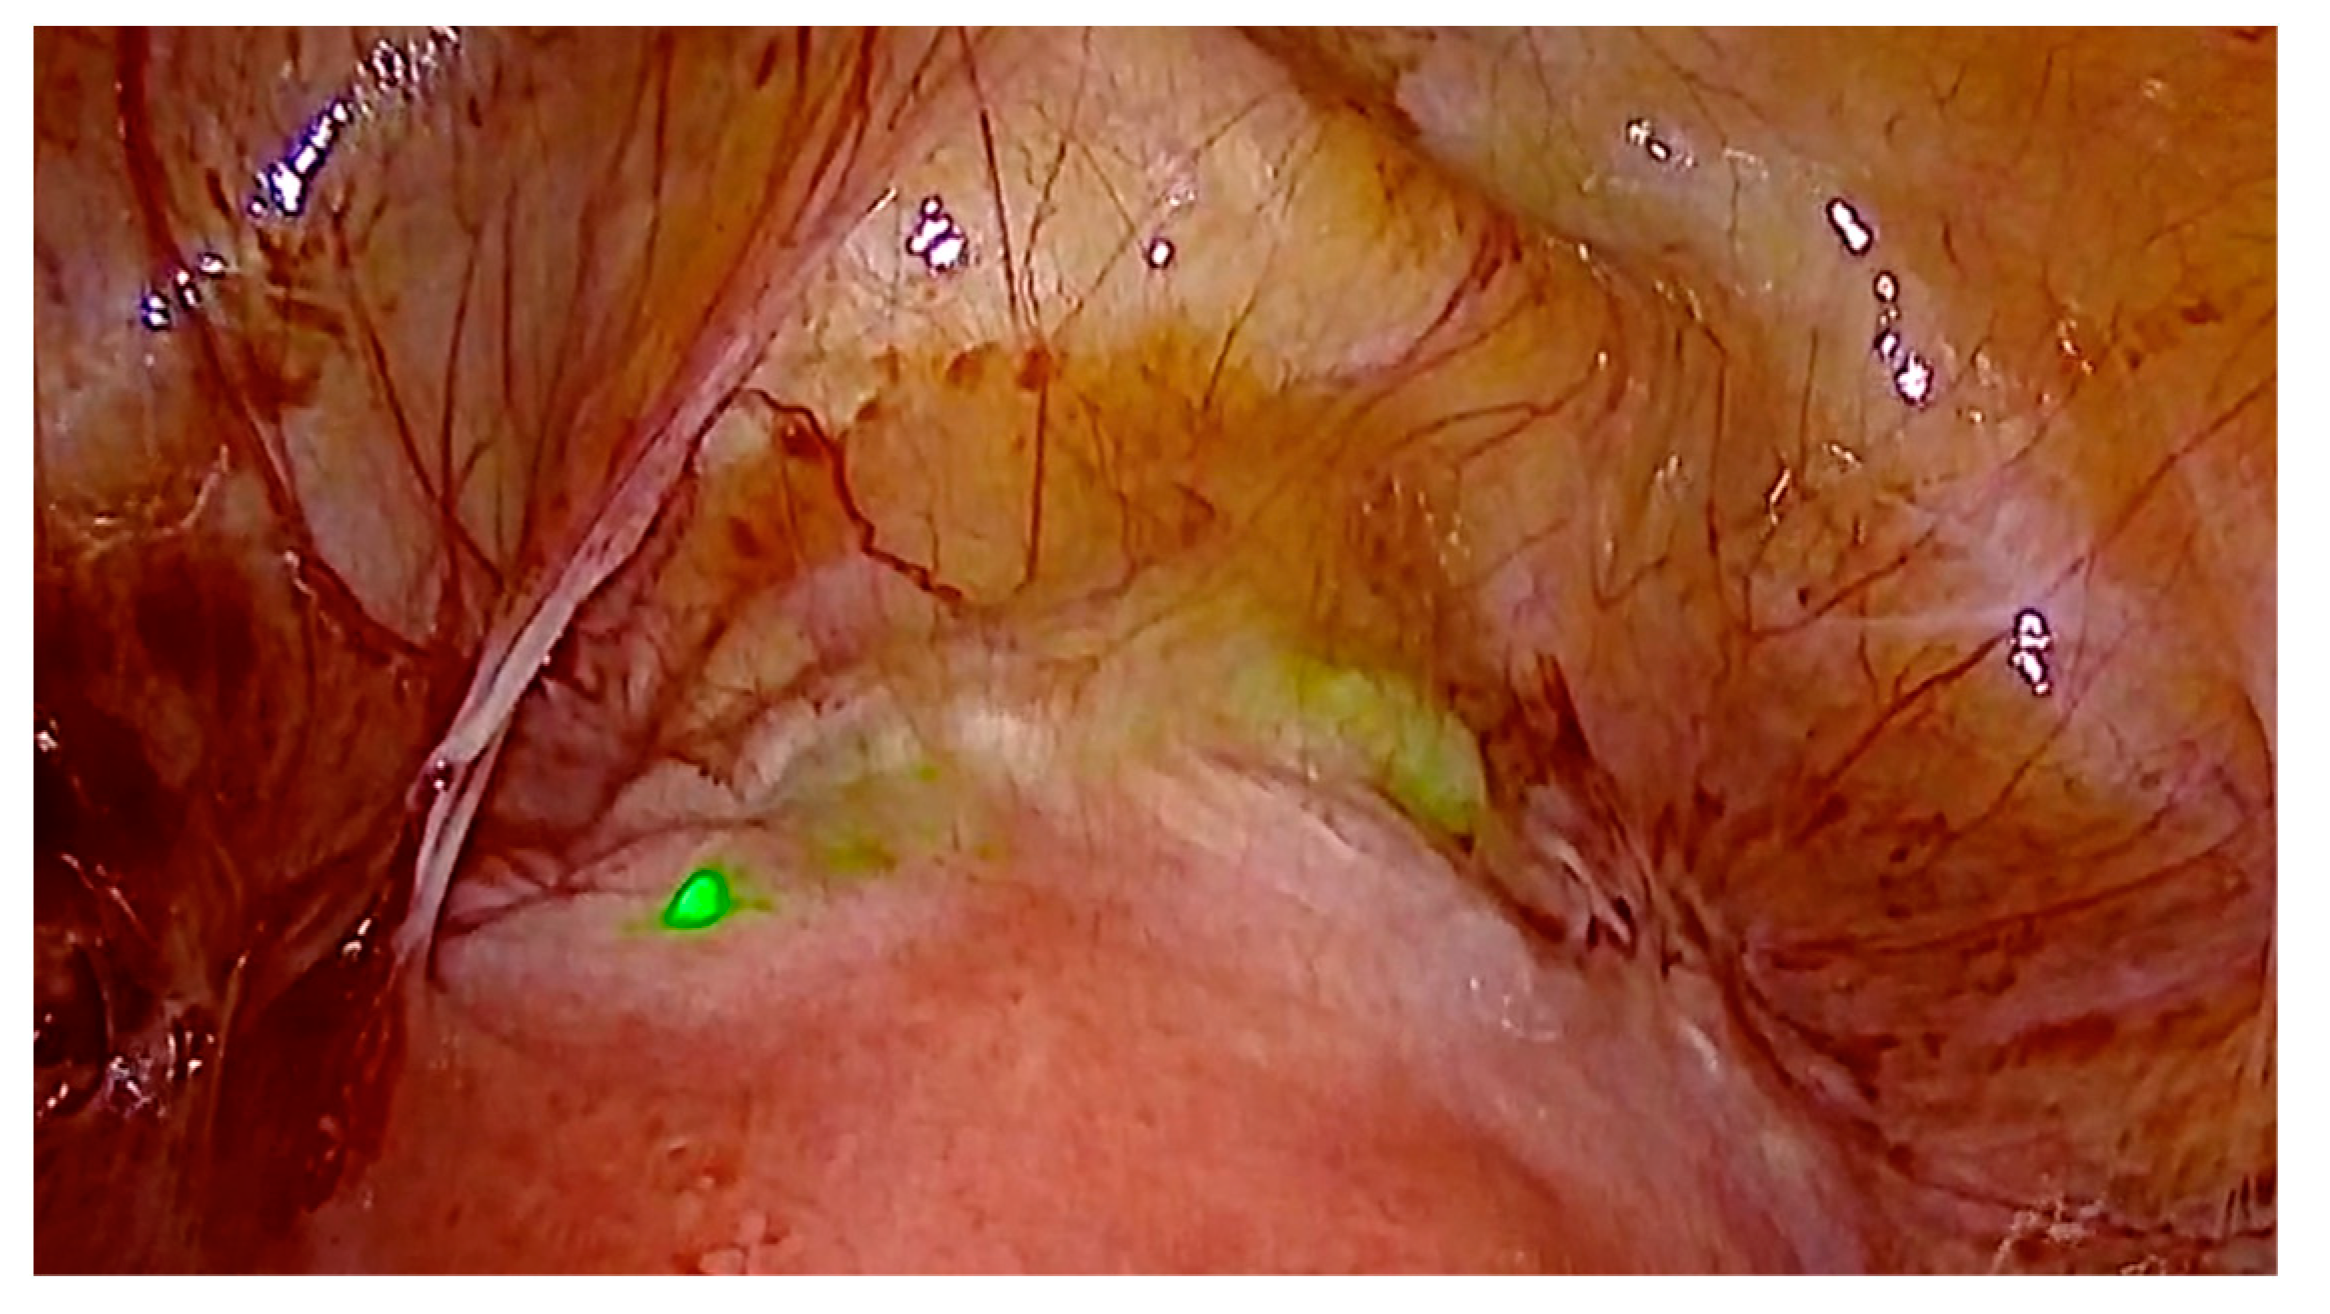

3.1. Case 1—Symptomatic Niche—Laparoscopic Treatment with ICG Niche Detection